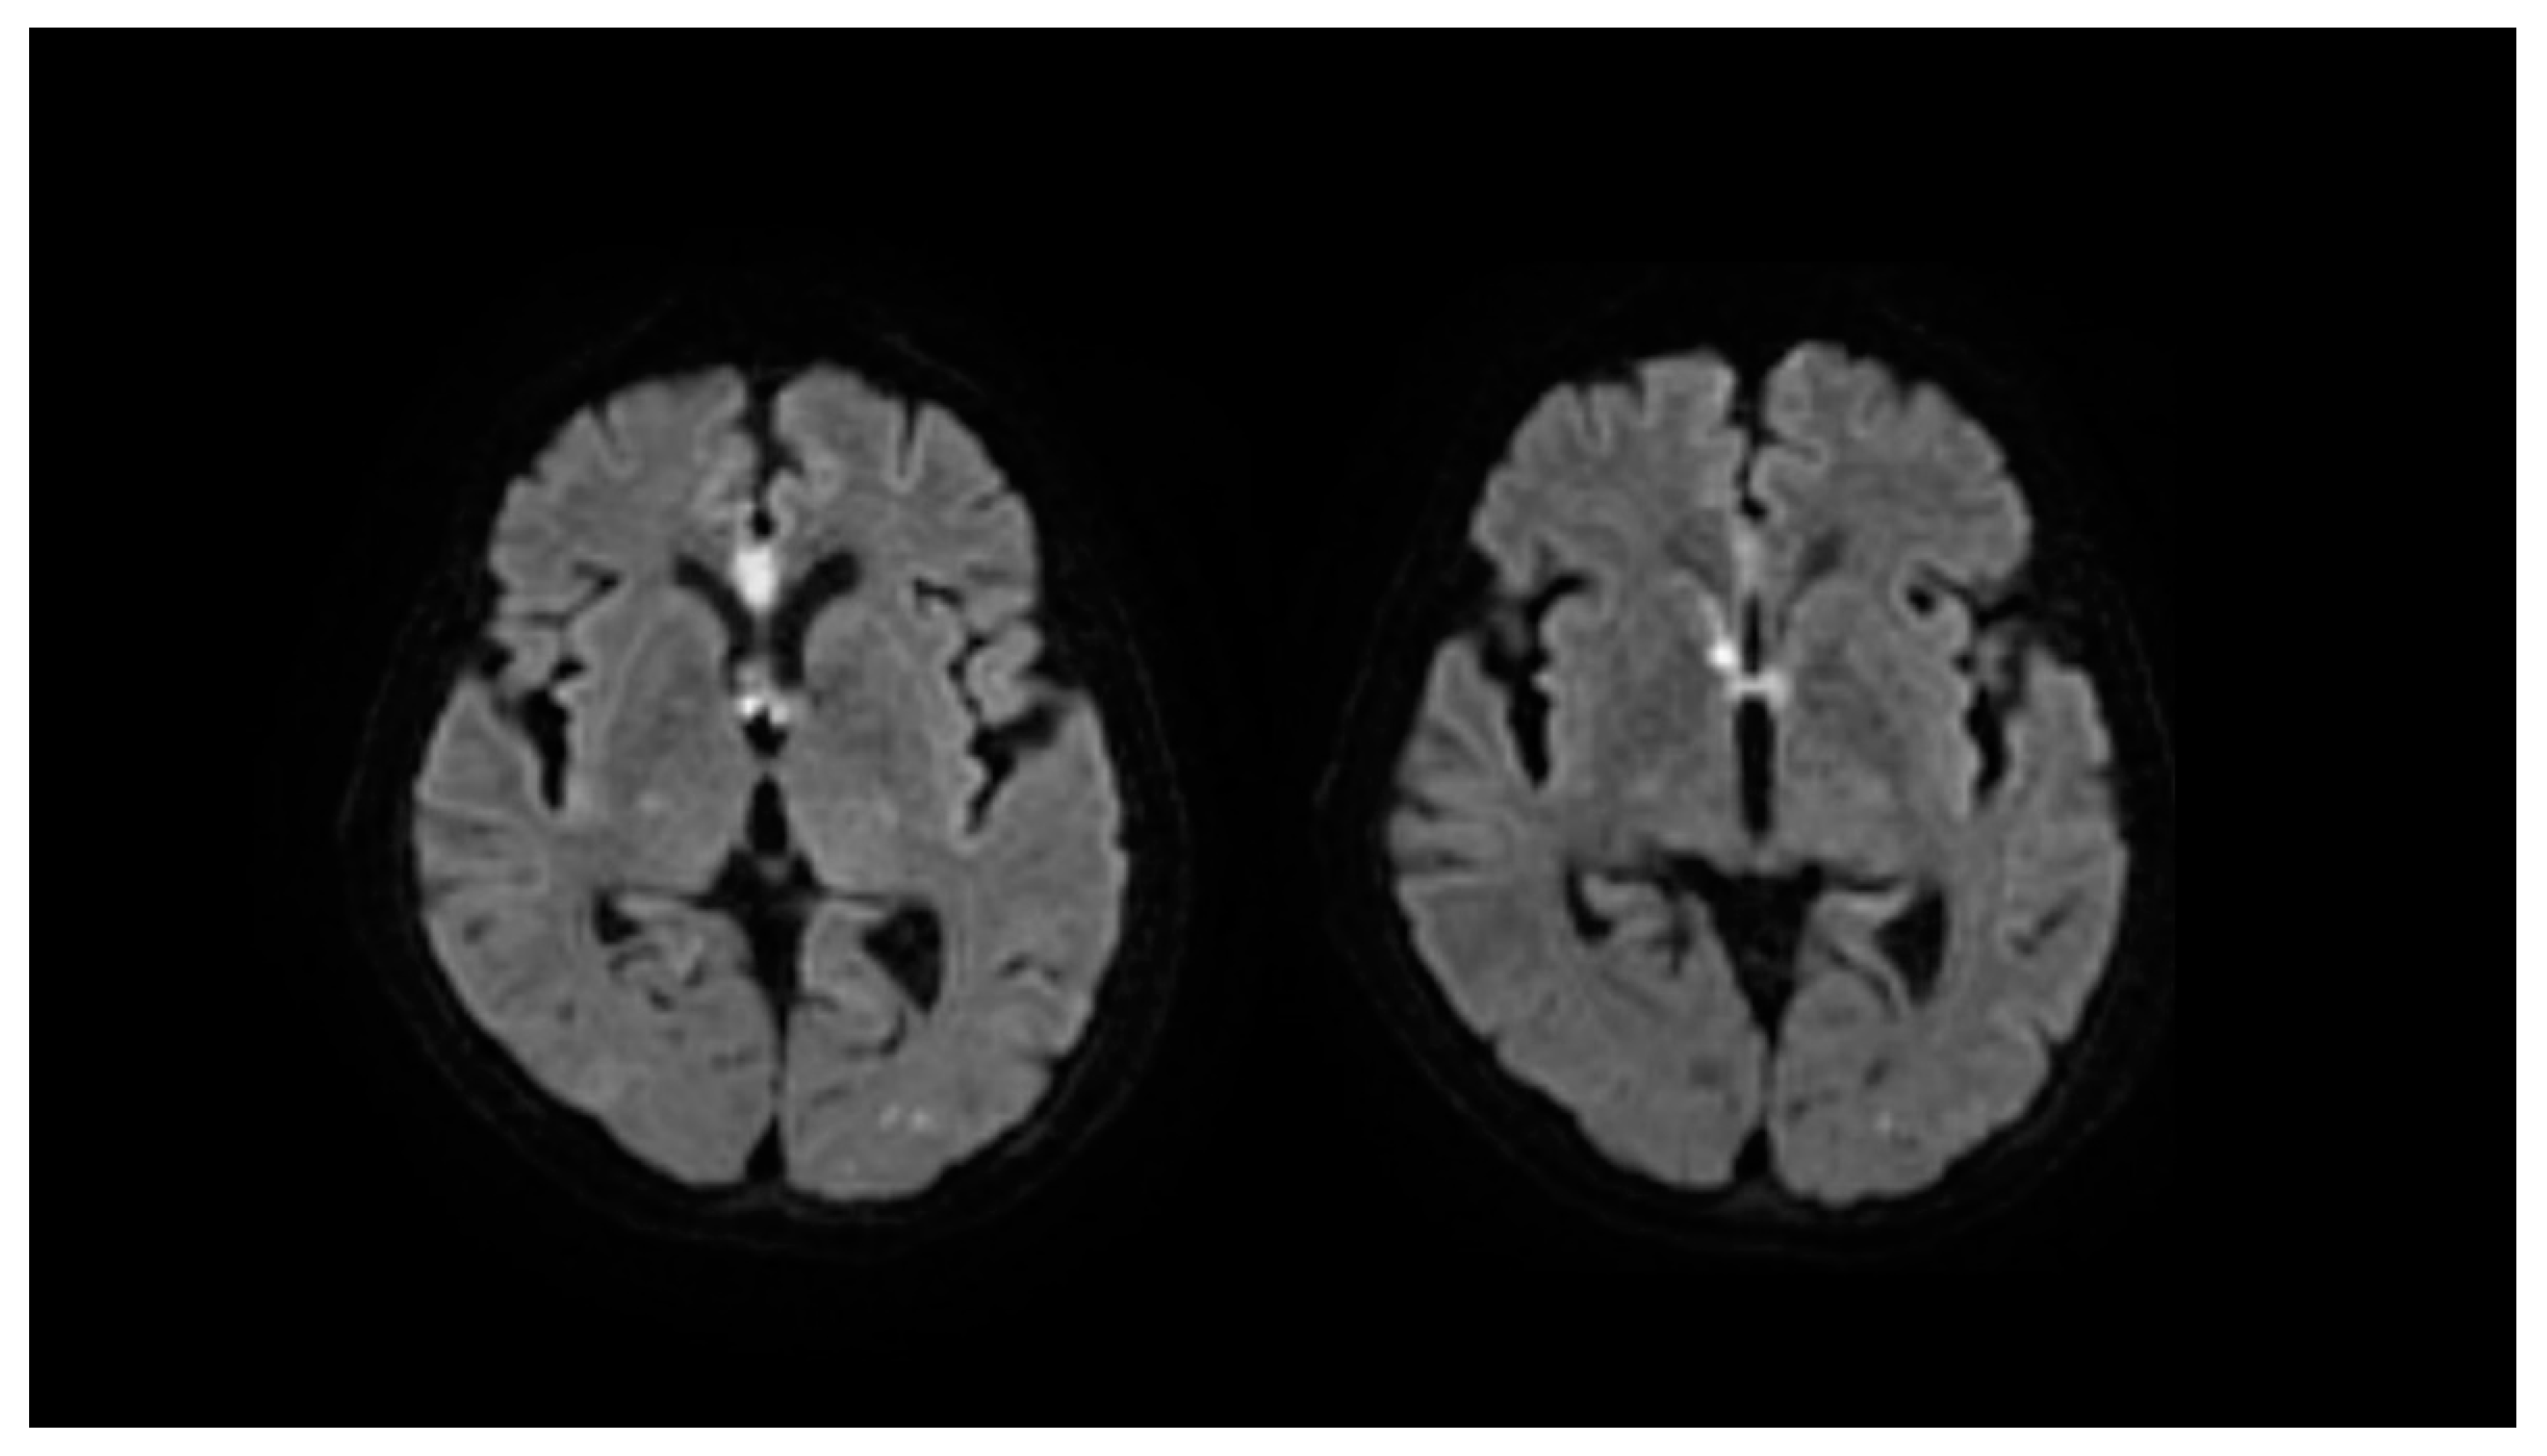

3.3. Our Case